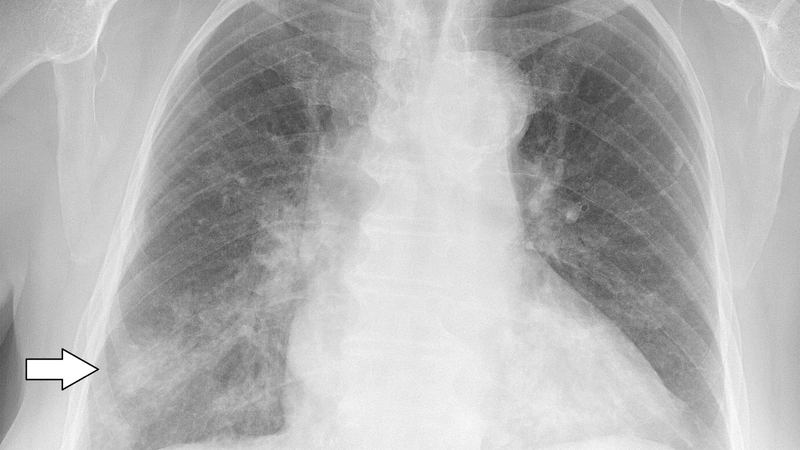

Bệnh nhân thực hiện chụp X quang ngực để tạo ra hình ảnh cụ thể các bộ phận trên cơ thể con người. Qua hình ảnh phim thu được, bác sĩ sẽ tiến hành phân tích, đọc kết quả và chẩn đoán bệnh lý mắc phải.

Chụp X quang được ứng dụng chủ yếu trong chẩn đoán các bệnh lý về xương và phổi con người. Đặc biệt là các bệnh có liên quan đến hô hấp. Đây là phương pháp xét nghiệm cận lâm sàng quan trọng. Kết quả bệnh sẽ được bác sĩ đọc dựa trên phim X quang được chụp trước đó. Vậy các bước đọc X quang ngực cơ bản là gì? Hãy theo dõi các thông tin được cung cấp trong bài viết này.

Chụp X quang ngực là phương pháp kỹ thuật sử dụng chủ yếu để chẩn đoán và đánh giá tình trạng của ngực, thành phần và cấu trúc lân cận thông qua hình ảnh phim thu được.

Kỹ thuật chụp phim này được ứng dụng nhiều trong y khoa. Dựa trên đó, các bác sĩ có thể phân tích, đánh giá và phát hiện các bất thường trong ngực. Sau đó, bác sĩ tiến hành đưa ra các chẩn đoán bệnh sơ bộ.